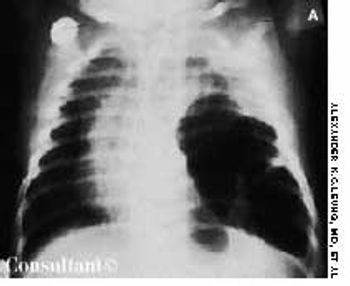

An irritable, lethargic, toxic-looking, and slightly cyanotic 2-month-old boy had a temperature of 40°C (104°F), malaise, and a cough for 2 days. The infant's heart rate was 98 beats per minute, and his respiratory rate was 55 breaths per minute. He had nasal flaring, sternal and subcostal retractions, diminished breath sounds, and scattered rales over the left lung, which was dull to percussion.